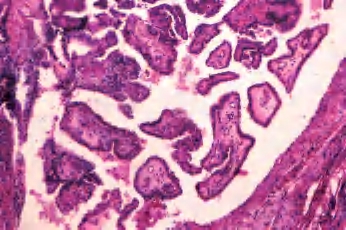

(2)大滤泡亚型:罕见,主要或全部由大滤泡构成,常与增生性结节或大滤泡腺瘤混淆;但滤泡细胞含有大而亮的核和核沟、核内假包涵体。此亚型很少见到淋巴结转移(图3-46、图3-47)。

图3-46 甲状腺乳头状癌,大滤泡亚型

图3-47 甲状腺乳头状癌,大滤泡亚型